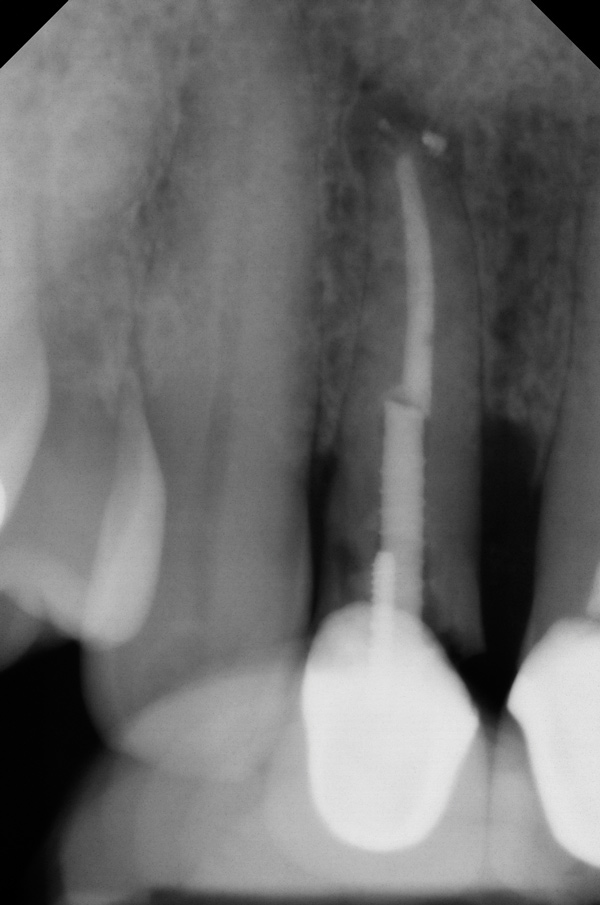

Fig 1. Clinical photograph showing significant issues related to implant midfacial mucosal recession and loss of interdental papillae. This is attributed to incorrect implant positioning (too buccal and too deep); several corrective surgeries resulted in interproximal bone loss, then loss of interdental papillae.

Figure 1

Fig 2. Radiograph showing implant was placed too deep and the diameter of the implant may be slightly larger than what was needed.

Figure 2